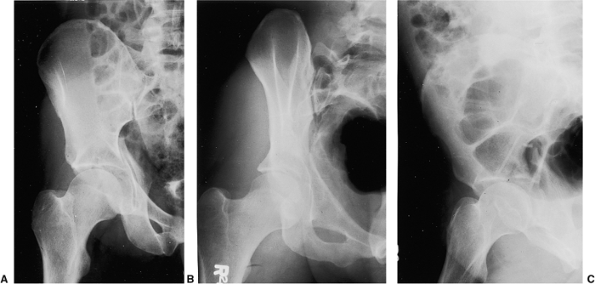

![]() |

Figure 41.47. A,B. Selected preoperative two-dimensional CT sections through the dome and columns of the acetabulum.

|